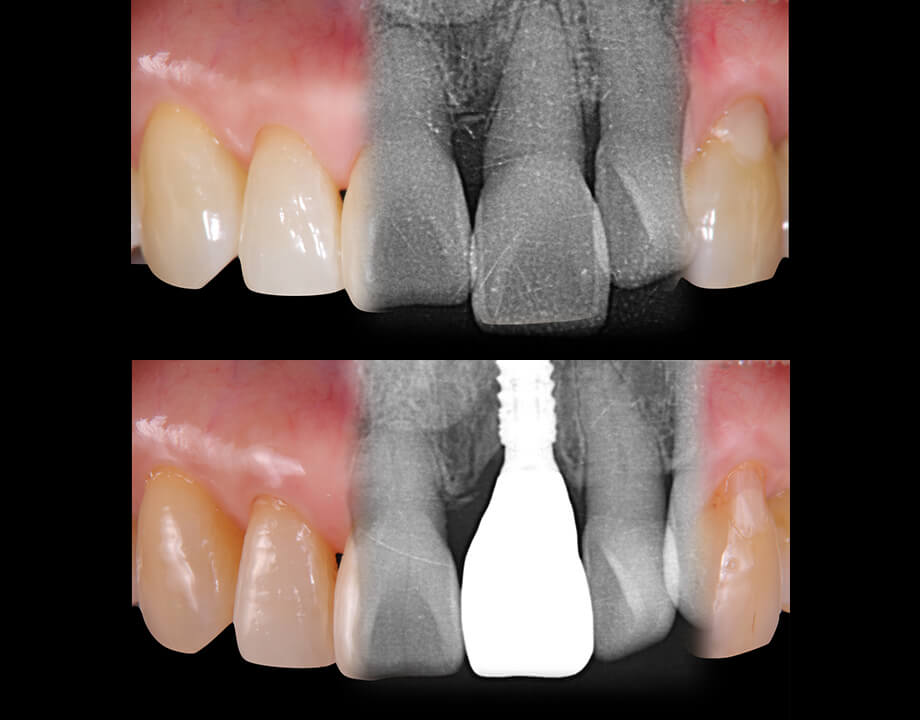

インプラント

当技工所はインプラント補綴に特化しており多様な症例に柔軟に対応可能です。

スクリューリテイン、セメントリテイン、カスタムアバットメントなど設計提案からのご相談にも対応いたします。

インプラント治療におけるコンピューターガイドシステムの一つで、CT診断によるシミュレーションを実際の口腔内で再現いたします。

これにより、より正確なインプラント埋入が可能になり、患者の負担を軽減する手術(フラップレス手術)も行える場合があります